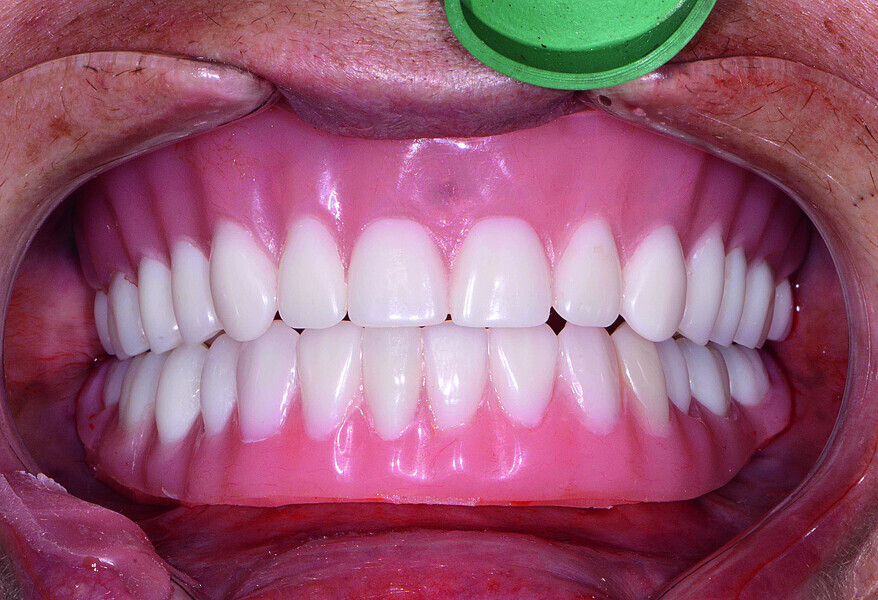

Fig. 22: Post-op retracted closedbite

view.